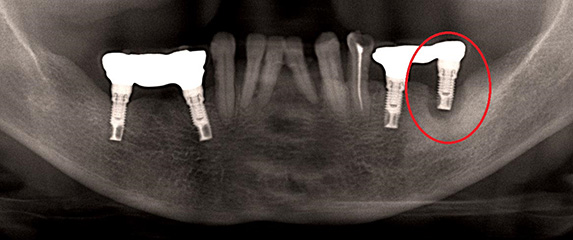

ここにある写真は、インプラント周囲炎を主訴として、よしの歯科クリニックへ来院された患者様のお写真です。(尚、患者様から許可を得て載せています。)向かって右下の奥に円があるところのインプラントの周囲の骨がなくなっている状態です。さらに、重度のインプラント周囲炎により保存不可能と診断しインプラントを撤去した時のお写真です。